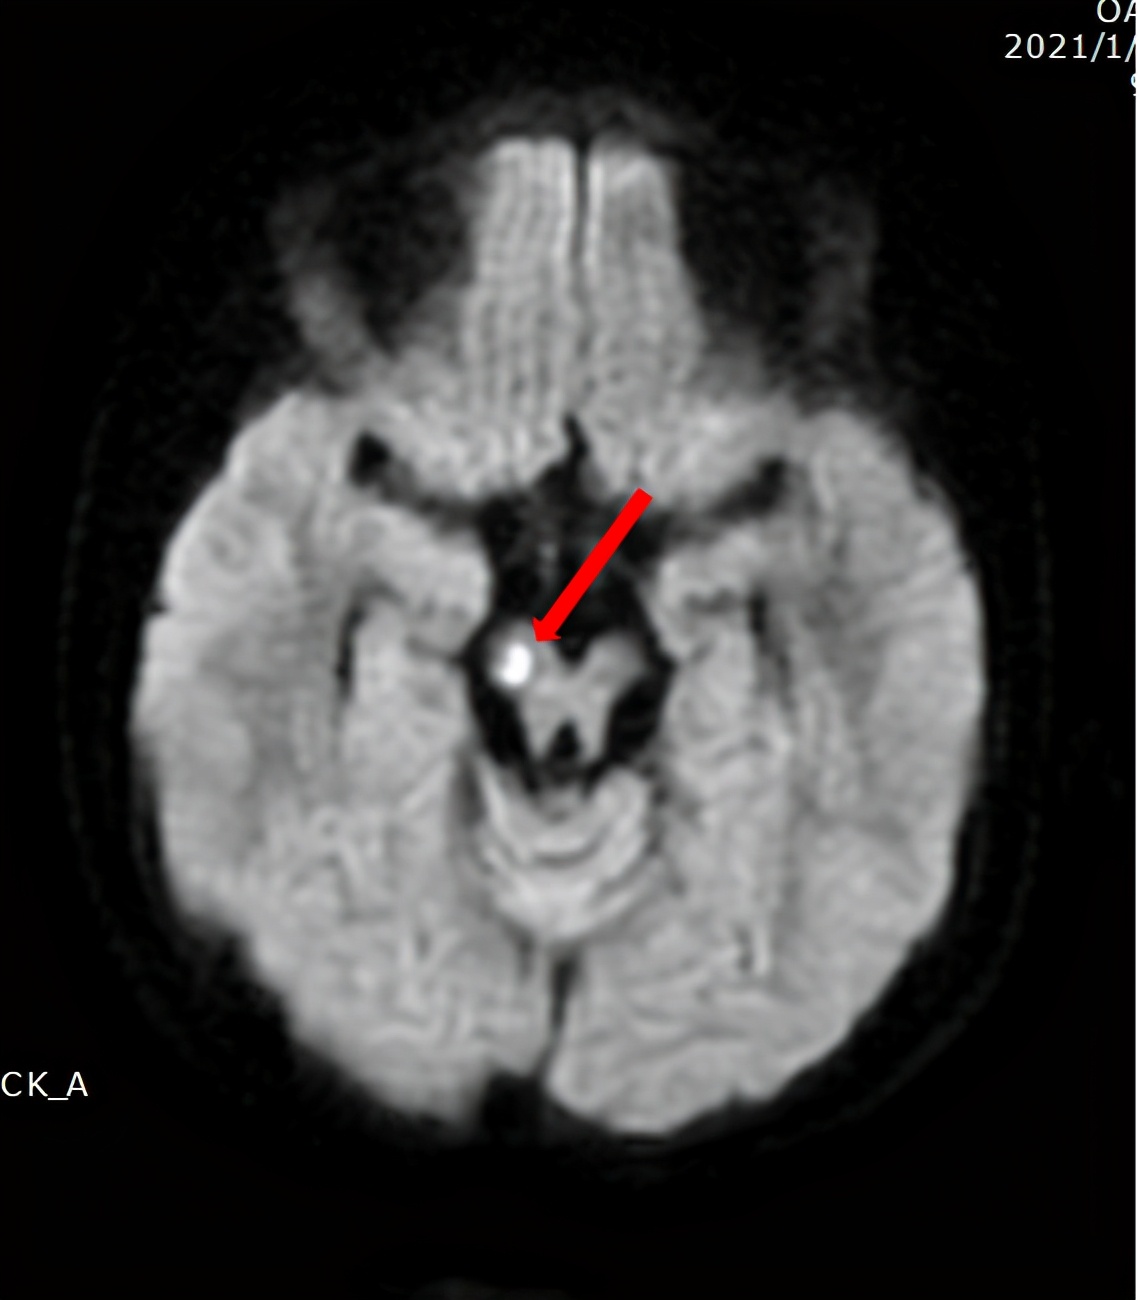

总结小慧的临床表现,发现其皮肤、神经、免疫系统都有相应症状。再结合其头颅影像学以及基因检测结果,支持ADA2缺乏综合征的诊断。

经儿童神经、遗传、内分泌科和儿童影像中心多次讨论分析,考虑到小慧的病程时间长,成发作性病程,且出生没多久就出现了症状,考虑“先天性疾病”的可能性大,建议进一步完善头颅功能核磁和相关基因检测。